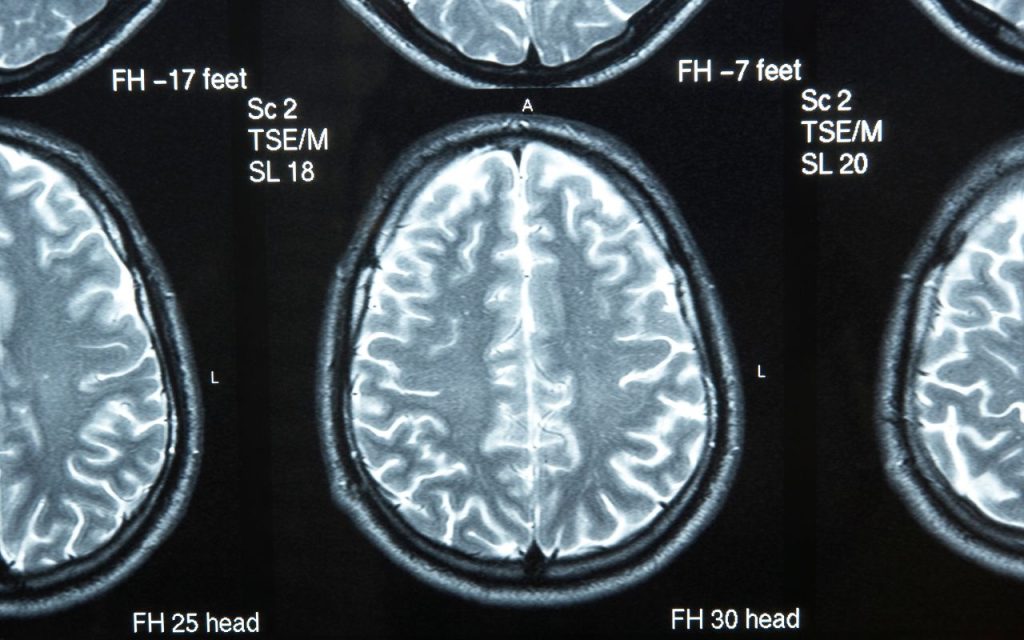

Als je je zorgen maakt, is het altijd goed om naar de huisarts te gaan. Vooral als je merkt dat je geheugen of andere cognitieve functies achteruitgaan, of als je familieleden hebt met dementie. De huisarts kan je doorverwijzen naar een neuroloog voor verder onderzoek. Een MRI-scan kan bijvoorbeeld helpen om de omvang van de corticale atrofie te bepalen. Het is niet eng, het is gewoon een foto van je hersenen, alsof je een vakantiekiekje maakt!